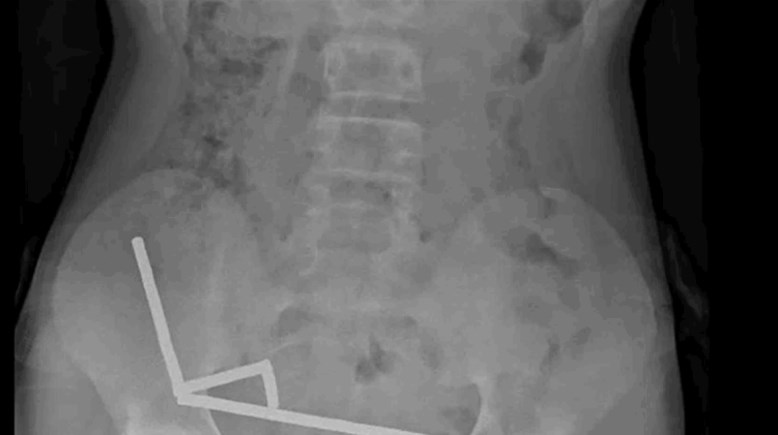

مراهق يبتلع 100 قطعة مغناطيس، ماذا حدث لأمعائه؟